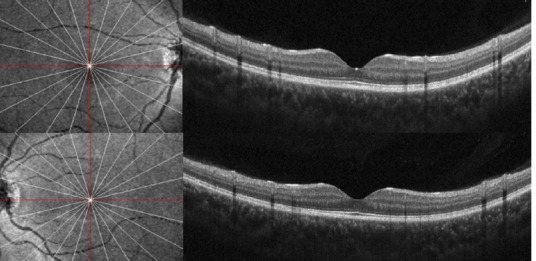

Results: A 14-year-old girl with no significant medical history reported several weeks of blurred vision in both eyes. She had been using 2% topical minoxidil on her eyebrows and eyelashes without a prescription for the past 6 months. The initial examination revealed that the best-corrected visual acuity (BCVA) was 20/80 in the right eye and 20/25 in the left eye, with no abnormalities noted in the anterior segment. Fundus evaluation and OCT confirmed bilateral serous retinal detachment. Given the patient's unsupervised minoxidil use, a causal link to central serous chorioretinopathy (CSC) was suspected. After discontinuing the drug, the subretinal fluid (SRF) resolved, and visual acuity fully recovered within three months, supporting the association between minoxidil and choroidal neovascularization (CNV), not CSC.